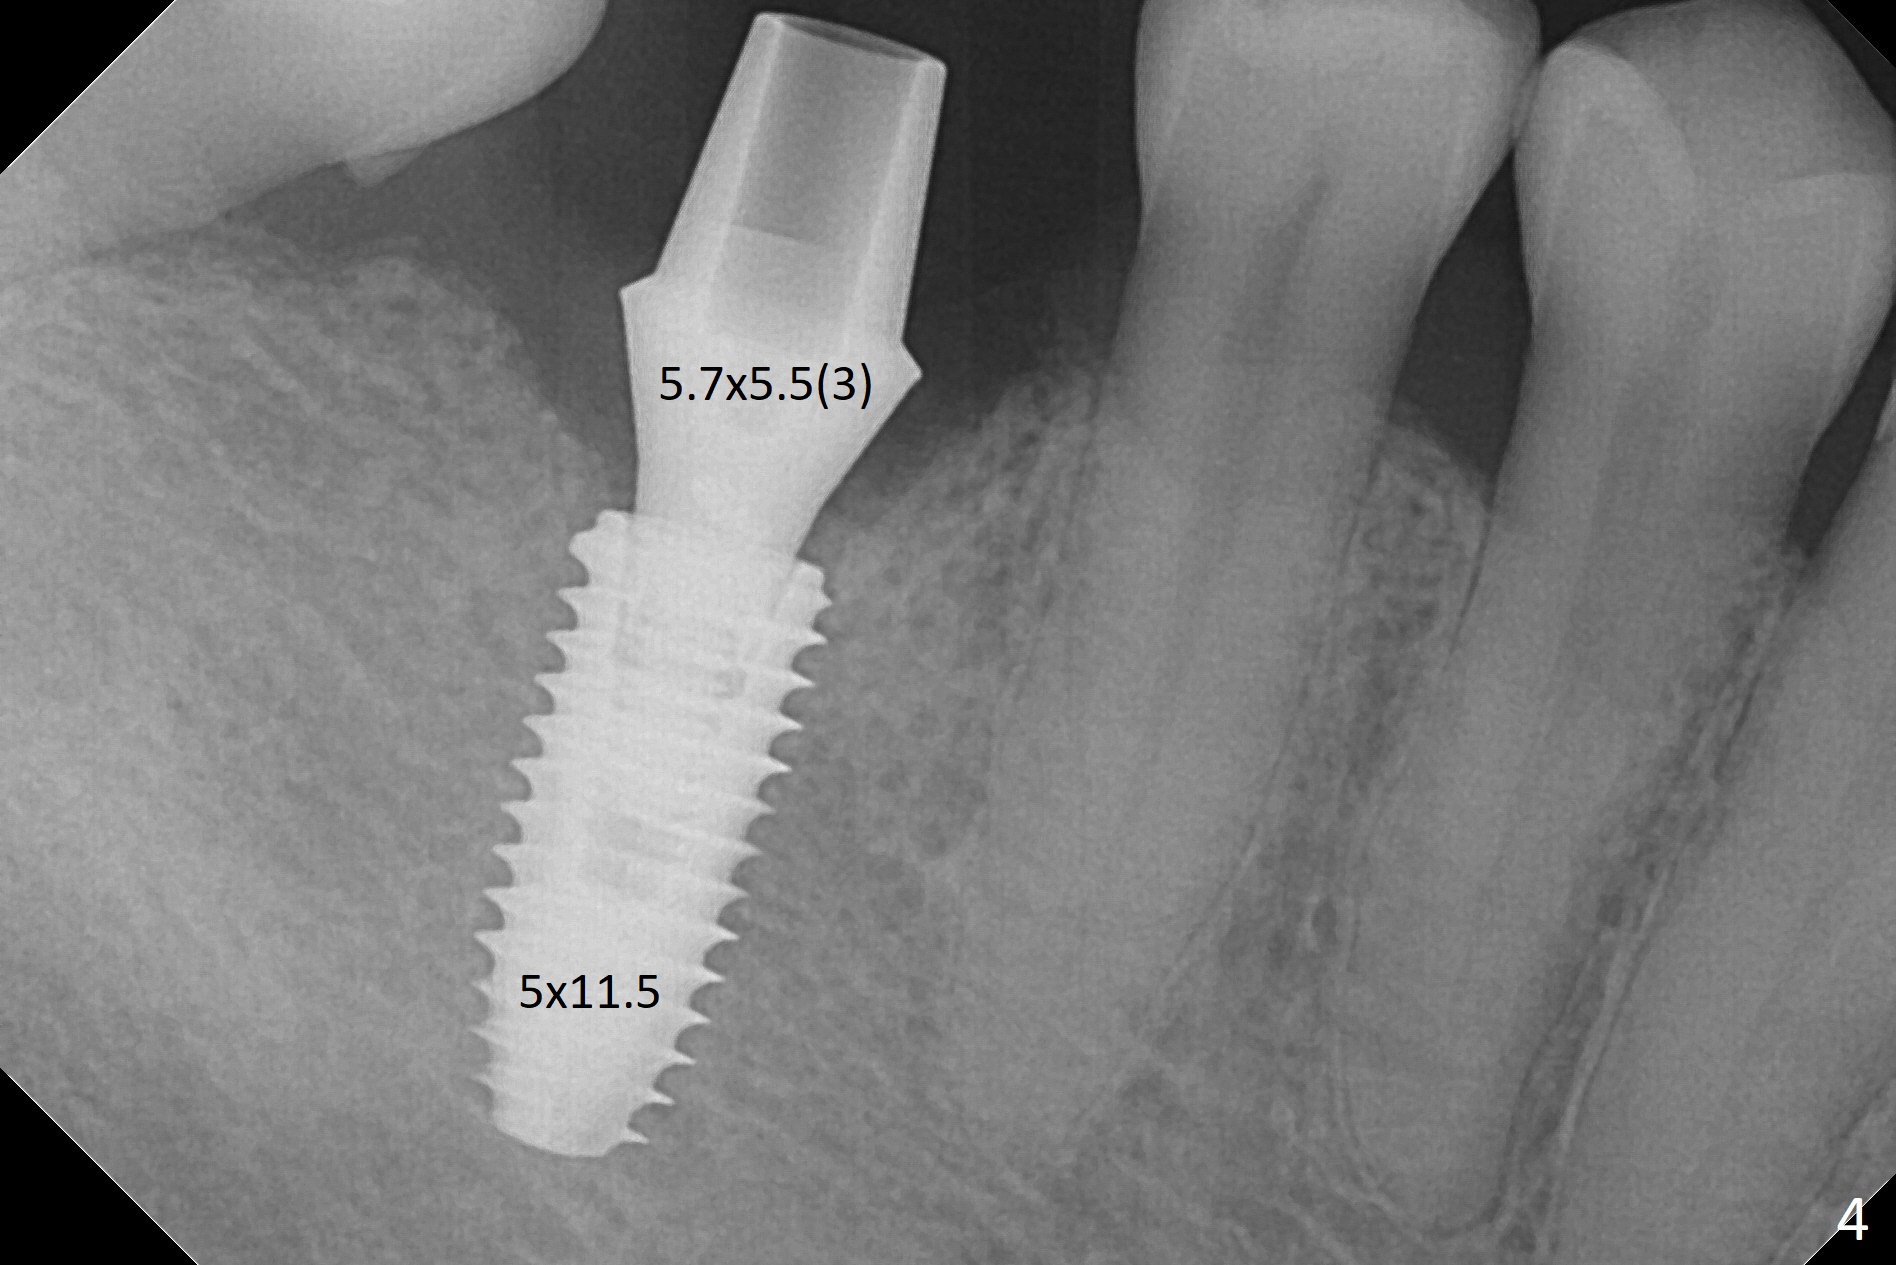

When the residual roots of the tooth #30 (Fig.1) are removed, the buccal crest is found ~ 2 mm apical to the lingual one (Fig.2 <); while the initial depth of osteotomy is 11.5 mm (yellow lines), the parallel pin is 10 mm long. To place a 5x11.5 mm implant at the level of the buccal crest (Fig.4 (>45 Ncm)), subsequent osteotomy depth is 13 mm using the lingual crest as a landmark (Fig.3 (4 mm drill in place)). After insertion of a 5.7x5.5(3) mm abutment, Vanilla Graft is placed (Fig.5 * with 2 mm buccal gap). The abutment with a provisional is loose 4 months postop (Fig.6). The permanent restoration is cemented 6 months postop. The abutment screw is loose and fractured 8 and 11 months post cementation, respectively (Fig.7). The fractured screw seems to be loose within the implant well and is easily re-winded out using Screw Removal Kit (sr-kit.html). When the crown/abutment at #30 is loose 2nd time 1 year 7 months post cementation (Fig.8 taken post retightening), the screw at #19 fractures. The tooth #2 needs a crown. The patient cannot use the anterior teeth, since the teeth #8 and 9 have root fracture. Can extraction and bone graft increase bone height? The screw re-fractures 9 months later (Fig.9). The dislodged crown is sectioned; the abutment is reseated completely (Fig.10) for a new crown. The tooth #2 needs RCT, B-U and crown, while the tooth #1 extraction (Fig.11).